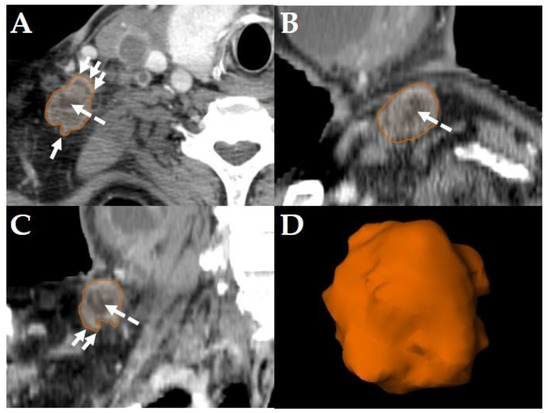

All diagnostic-, planning- and restaging-CTs were imported to the segmentation software (Elements, BrainLab, Munich, Germany). For each patient the three largest LNs were manually segmented in all data sets slice-by-slice in the axial plane using the “paint on slices” tool provided by the software. All segmented LNs were examined by two experienced, board certified head and neck radiologists with more than 15 years of clinical experience in head and neck CT reporting. The segmented LNs were classified as “pathologic” (Figure 2), “pathologic with ECS” (Figure 3) or “non-pathologic” (Figure 4), complying with current CT reading criteria for LN-malignancy [5,6,7].

Figure 2. Example of a LN classified as “pathologic” in a staging-CT of a 55-year-old, male HNSCC patient with a tumor of the oral cavity staged cT4a cN2b cM0. Original segmentation in the axial plane (A); sagittal (B) and coronal (C) reformatted views and three-dimensional rendering (D) of the LN are provided by the software. Dashed arrows show central necrosis; no soft tissue infiltration and irregular LN capsule was observed.

LNs were classified “pathologic” in staging- and planning CTs, if axial diameters were >10 mm, LN margins were poorly defined, capsular contrast agent enhancement and/or central necrosis was observed [5]. LNs were classified “pathologic” if in restaging-CTs (i.e., after primary concurrent RCT), the maximum short axis LN diameters was >10 mm, focal LN abnormalities (lucencies, contrast-enhancement or eccentric LN bulging) were observed, and/or if an increase of the maximum short axis LN diameter of >2 mm in restaging-CTs was observed [6] (Figure 2).

Consequently, the classification of the segmented LNs in “pathologic” (Figure 2), “pathologic with ECS” (Figure 3) and “non-pathologic” (Figure 4) by the two experienced head-and-neck-radiologists based on established criteria [5,6,7] was defined as reference.